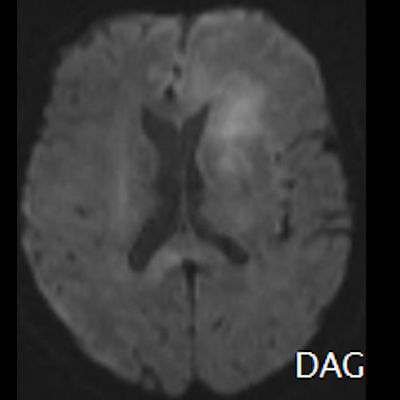

- (C) Difüzyon ağırlıklı görüntülerde sol frontaldeki kitle lezyonunda difüzyon kısıtlama bulgusu (oklar) mevcut olup perfüzyon MRG’de rCBV haritasında belirgin perfüzyon artışı izlenmemektedir (ok).

- MRG’de, lenfomalar tipik olarak T2A sekanslarda hipointens olup DAG’de belirgin difüzyon kısıtlanması gösterirler.

- T2 sinyali belirgin düşük olgularda b=1000 görüntülerde hipointens görünüm izlenebilir ve T2 kararması (T2 black-out) etkisi olarak adlandırılan bu durum yanlış yorumlamalara yol açabilir. Bu nedenle gerçek difüzyon kısıtlamasını değerlendirmede ADC haritaları daha güvenilirdir.